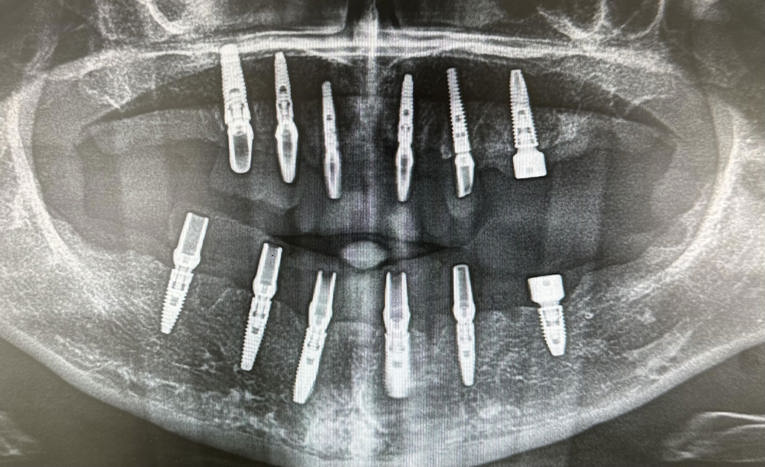

Dentalni implantati ugrađuju se u čeljust i njihovo učvršćivanje traje 3 do 4 mjeseca – kontrolira se rendgen slikom.

Kontrola rendgen slikom. Foto: Dental Centar Jelić

Postupak se izvodi u lokalnoj anesteziji i potpuno je bezbolan. Ukoliko je potrebo ugraditi više implantata, ugrađuju se istovremeno u jednoj posjeti. Nakon 3 do 4 mjeseca vrši se kontrola učvršćivanja i pristupa se izradi keramičkog mosta ili krunice.